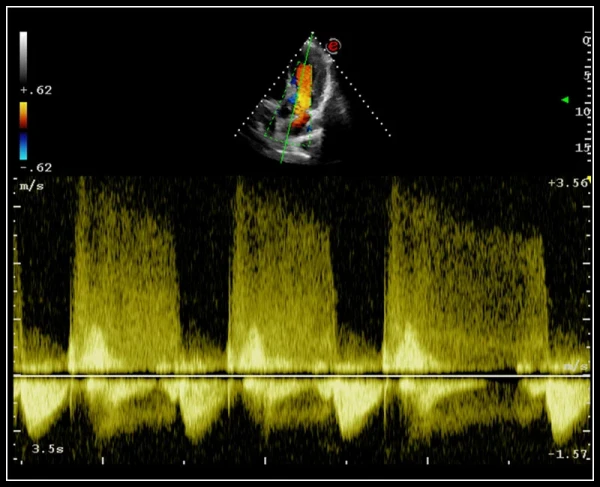

ULTRA-Color Doppler rangli xaritalash usullari: yuqori sezuvchanlik, chuqur kirish va yuqori aniqlik

QPack. Doppler rejimlarida va CnTI kontrastli tasvirlash texnologiyasidan foydalangan holda kontrast agenti perfuziyasini miqdoriy baholash uchun yangi vosita

EasyTrace algoritmi. Doppler rejimlarida vizualizatsiyani avtomatik sozlash algoritmi, aks ettirish burchagini to'g'rilaydi va bir necha soniya ichida miqdoriy ma'lumotlarni taqdim etadi.